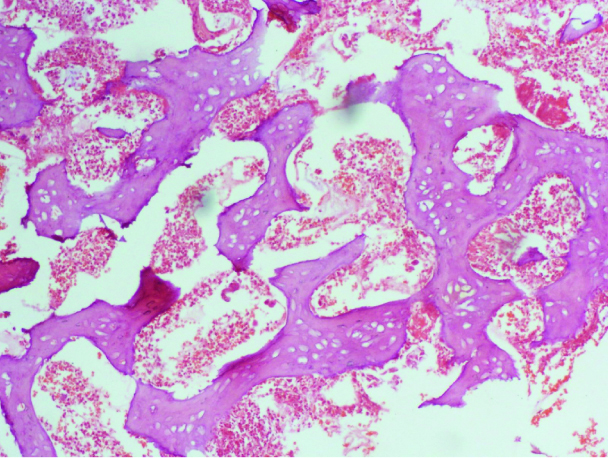

Photomicrograph showing well organised trabeculae of bony tissue (magnification x 100).

At presentation, speculum examination of the vagina and cervix revealed a smooth cervix; a tiny brownish hard tissue was seen at the external cervical os and sent for histology. Pelvic Ultrasonography (USS) done revealed a normal sized uterus and endocervical plaque probably bone fragment [Table/Fig-1]. Further evaluation of the endometrial cavity by hysteroscopy showed four bony fragments in the endocervical canal, which were removed. Mild adhesions were noted around the fundal region. She recovered without complications. The histology report [Table/Fig-2,3] revealed proliferative endometrium, fragments of bony tissue with marrow elements. She was reviewed at the gynaecological clinic 2 weeks following the procedure and there were no new complaints. At the sixth month, post-hysteroscopy, she presented with amenorrhoea of 6 weeks duration and a positive pregnancy test. Ultrasonography confirmed a viable 6-week intrauterine pregnancy. She was referred to the antenatal clinic for further management and her consent was obtained for the publication of the above findings.